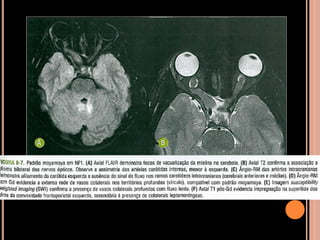

Área de vacuolização de mielina

 Origem é controversa;

 Achado típico em crianças com NF1;

 Focos hiperintensos em T2 e no FLAIR em núcleos

da base, cápsula interna, tronco encefálico e

cerebelo;

 Mais comum no globo pálido, geralmente bilateral;

NF1

Vacuolização de mielina

 Aparecimento geralmente aos 3 anos  aumenta

até os 12 anos  tendência a regredir;

 Raro observar após os 20 anos de idade;

 Alterações cerebrovasculares são incomuns;

 Estenose, aneurismas; malformações

arteriovenosas, hipoplasia das artérias carótidas

internas;

 Difusão importante para detectar isquemia

parenquimatosa aguda;